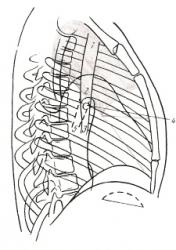

Ниже приведены схемы спадения долей и сегментов (по Anacker H., 1963) – иллюстрации 11, 12, 13.

Для своевременной диагностики, как долевых, так и сегментарных ателектазов необходимо уделять внимание следующему:

- положение и наличие деформации междолевых и межсегментарных щелей;

- степень спадения отдельных структурных единиц лёгкого;

- закономерности их перемещения при спадении;

- состояние окружающих тканей лёгкого;

- возможности перемещения диафрагмы, средостения и здорового лёгкого – иллюстрация 14.